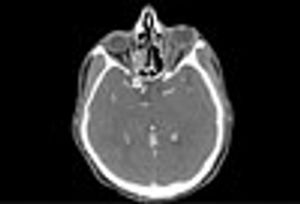

A 58-year-old man with a past medical history of chronic sinus disease and hypothyroidism presented with left periorbital pain and erythema that worsened despite outpatient treatment with topical antibiotics. An outpatient CT scan showed pansinusitis and orbital stranding. The diagnosis was orbital cellulitis and sinusitis.